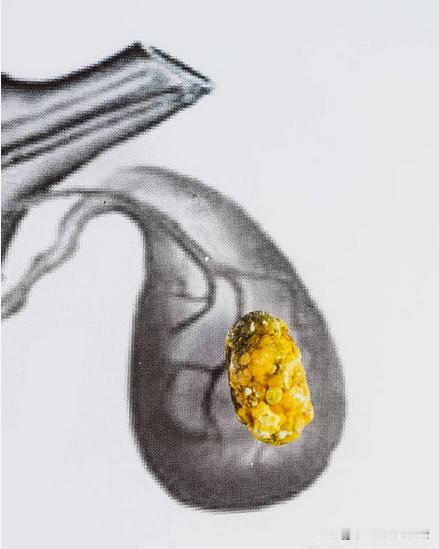

胆结石患者,体内湿热瘀阻 在行医的这些年里,我见过许多被胆结石困扰的患者。他们有的疼得满地打滚,有的只是偶尔感到不适,但无一例外,他们的生活都被这小小的石头搅得一团糟。 今天,我想和大家聊聊胆结石的真相,以及如何来解决这个问题。 先给大家讲一个真实的故事。有一位患者,我们叫他老李吧,他被胆结石折磨了七八年。刚开始,他只是偶尔感到右上腹有点胀痛,以为是吃坏了肚子,没太在意。后来,疼痛越来越频繁,还开始恶心呕吐,这才去医院检查,发现自己长了胆结石。 老李试过各种方法,西药、手术都考虑过,但要么效果不明显,要么害怕手术风险。一次偶然的机会,他看到了我分享的中医治疗案例,抱着试试看的心态来找我。经过详细的问诊,我发现老李的胆结石问题,其实和他平时的生活习惯有很大关系。 脾胃失调:胆结石的幕后黑手 在中医里,脾胃被称作“后天之本”,意思是人出生后,脾胃就像一个大厨房,把吃进去的食物变成身体需要的气血和营养。如果脾胃出了问题,身体就会像缺了油的机器,慢慢出故障。 现代人生活节奏快,饮食不规律,喜欢吃肥甘厚味、油炸食品,这些都很容易伤脾胃。脾胃一旦虚弱,就没办法好好工作,水湿就会在身体里堆积,变成湿热瘀阻。而胆腑和脾胃通过经络相连,湿热瘀阻就会顺着经络跑到胆腑,把胆腑的气血通道堵住,胆汁分泌不畅,时间一长,胆结石就形成了。 中医:清热利湿,化瘀通络 那中医是怎么解决胆结石的呢?其实很简单,就是找到病因,对症下药。中医会根据每个人的具体情况,通过调整脏腑功能、清热利湿、活血化瘀等方法,让身体恢复到正常状态。 比如,老李的情况,我就给他开了一个调理脾胃、清热利湿的方子。同时,我还教了他一些日常调理的小方法。几个月后,老李的症状明显改善,胆结石也小了很多。 日常调理:从生活点滴做起 其实,预防和缓解胆结石,关键还是要从日常生活做起。 饮食上,尽量少吃油腻、辛辣的食物,多吃蔬菜水果和粗粮,这样可以减轻脾胃的负担,减少湿热的产生。 运动也很重要,像散步、慢跑、瑜伽这些简单的运动,不仅能增强体质,还能帮助脾胃更好地运化水湿。 保持好心情也很关键,因为情绪不好也会影响脾胃功能,进而影响胆腑。 定期检查也很重要,尤其是有胆结石家族史或者已经查出有胆结石的人,要定期做B超检查,及时了解病情变化。